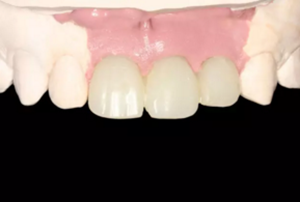

圖16 軟組織成形后口內(nèi)像

圖23 最終修復(fù)后即刻口內(nèi)像

圖25 最終修復(fù)后復(fù)查口內(nèi)像